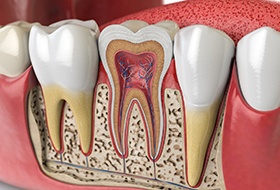

The Root Canal Process

As we mentioned above, the first step of the root canal procedure is always to numb your mouth thoroughly. Once you are comfortable and ready to begin, your dentist will use special tools to access the inner chambers of the tooth and remove the pulp. Then, they will sanitize the area, fill it with a synthetic gutta-percha material, and place a temporary crown over top. Once we receive your custom dental crown from the lab, we will secure it in place, officially completing the treatment process.